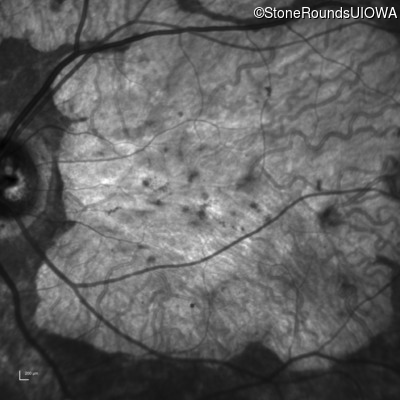

| AR Stargardt Disease | ABCA4 | Cys205Phe TGC>TTC | Gly863Ala (G)GA>(G)CA | AR |